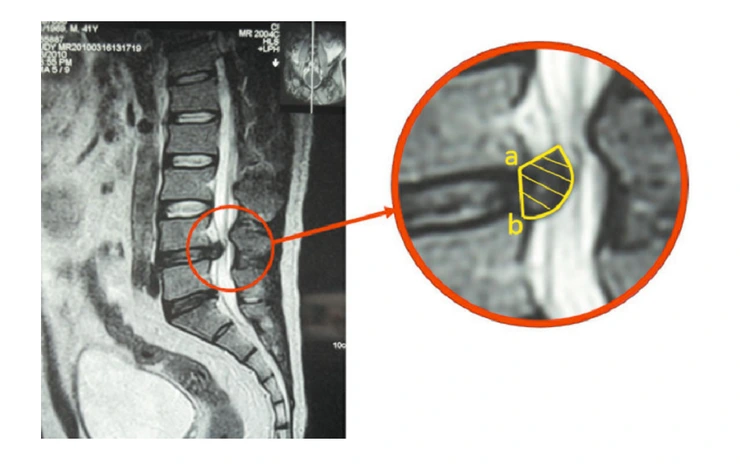

이 논문의 가장 큰 특징은 MRI를 촬영해서 디스크의 상하 단면적에서 가장 넒은 부위를 측정하면서 F/U했다는 것인데요, 위의 사진처럼 단면적 측정을 여러부위를 하여 부피를 계산해내는 방법을 사용하였습니다.